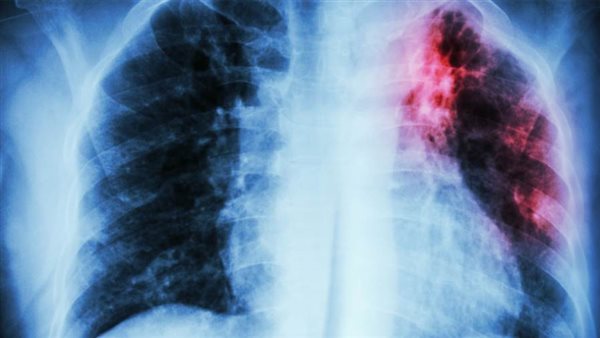

ففي كل عامٍ، يصاب 10 ملايين شخص بالسل على مستوى العالم، والسل مرضٌ معدٍ يصيب الرئتيْن بشكل رئيسي، ولكنه يستطيع مهاجمة أي جزء آخر من أجزاء الجسم. ويقتل السل 1.5 مليون شخص كل عامٍ على الرغم من أنه مرض يمكن الوقاية منه وعلاجه - مما يجعله أكثر الأمراض المعدية فتكًا بالبشر في العالم، ويُعدّ السل أيضًا السبب الرئيسي للوفاة في صفوف المتعايشين مع فيروس العوز المناعي البشري، وأحد العوامل الرئيسية التي تسهم في مقاومة مضادات الميكروبات على الصعيد العالمي. وفي عام 2022، أصيب 856,000 شخص بالسل، وتوفي 84000 شخص من جرَّائه، وهو ما يمثل 8% و7% من حالات الإصابات والوفيات على مستوى العالم.